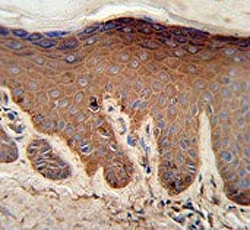

IHC testing of FFPE human skin tissue with Pyruvate Kinase PKM antibody. HIER: steam section in pH6 citrate buffer for 20 min and allow to cool prior to staining.